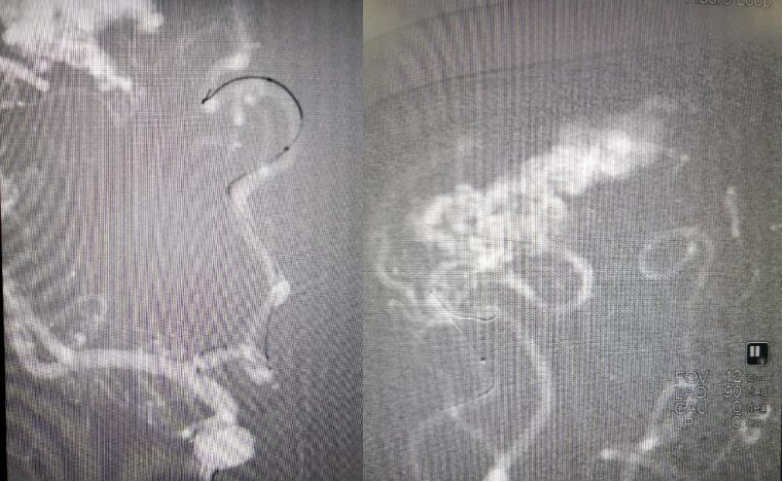

病情简介 主诉: 现病史: 既往史: 体格检查: 家族史: 辅助检查: 头颅CT DSA示供血动脉与引流静脉 右侧椎动脉 左侧颈内动脉造影,左侧大脑中动脉下干供血区动静脉畸形 左侧颈外动脉未向动静脉畸形供血 左侧椎动脉未参与动静脉畸形供血 手术方案: 手术指征: 右侧额顶叶动静脉畸形,左侧颞叶动静脉畸形 手术风险: 栓塞剂返流至颈内动脉导致异位栓塞 术中,术后颅内出血、癫痫等神经功能障碍 治疗过程: 来自大脑前动脉的分支为畸形血管团的一支供血动脉 微导管到位 微导管造影证实在供血动脉 弹簧圈栓塞供血动脉近端防止胶返流,然后注射胶栓塞畸形血管团 大脑前动脉供血的畸形血管团栓塞满意 畸形血管团的另一支供血动脉(来自大脑中动脉的分支) 注射胶栓塞畸形血管团 持续缓慢注射胶,胶逐渐弥散畸形血管团 供应畸形血管团的另一支供血动脉(来自大脑中动脉的另一分支) 持续缓慢注射胶,胶逐渐弥散畸形血管团 畸形血管团接近完全栓塞 标准正侧位造影畸形血管团接近完全栓塞,右侧颈内动脉系统血流通畅,无缺血区域 所用材料: 6F导引导管 ASAHI导丝0.010×200cm Echelon-10非解脱微导管 Apollo可解脱微导管 加奇弹簧圈 Onyx胶 术者思考 脑血管畸形也叫做血管瘤,但并非真肿瘤,是指先天性脑血管的异常发育,在胚胎期时,某些诱导因素导致脑部的血管网未正常发育,进而导致毛细血管发育不全,使动静脉直接相通,并造成短路,最终衍变成为畸形血管团,临床上分为动静脉瘤、先天性颅内囊性动脉瘤、静脉血管瘤及海绵状血管瘤等,其中以动静脉畸形最常见,其发病率达90%以上。脑动静脉畸形根据不同形态可分为以下几类:①动静脉畸形:此类畸形主要由动脉、异常血管、引流静脉组成,血管造影可清晰显示病灶结构,无毛细血管结构,病灶破裂后会引发颅内出血。②发育性静脉畸形:此类畸形主要由髓静脉先天发育异常引起,是目前最常见的一类脑动静脉畸形,一般发生于额顶叶处脑室旁白质或小脑半球处,影像学检查能够发现过度扩张的髓静脉呈扇形汇集至静脉干,两侧动静脉发育程度存在明显差异,髓静脉团形状类似“水母头”。③毛细血管扩张症:此类畸形属于较为罕见的类型,动静脉间毛细血管过度扩张形成团状,病灶较小,CT检查不易发现,一般发生于脑桥、小脑中脚和齿状核等位置。④海绵状血管瘤:此类畸形由大量薄壁血管组成,同样难以通过CT检出,MRI 检测病灶呈“爆米花”状,扫描信号也比较混杂,因其状态不稳定,经常导致反复少量的出血事件发生。临床症状主要为畸形血管破裂出血,“盗血”现象的发生可致局限性脑缺血,从而引起脑萎缩,患者智力会发生减退或出现精神失常。还包括搏动性头痛、癫痫以及偏瘫 、失语等。 其中以出血最为常见,若发生严重出血,出现脑疝,极有可能致死。目前,临床上对于脑血管畸形一般主要有手术切除 、血管内栓塞疗法、γ-刀治疗及放射治疗。作为传统治疗方法,外科手术切除不仅手术风险较高,并且术后患者的神经功能受损的几率较大。近年来,血管内栓塞疗法因其疗效确切、微创、并发症少的优点,已成为治疗脑血管畸形的重要方法。 在早期脑血管畸形治疗过程中,血管内介入栓塞治疗方法常被作为一种辅助性治疗手段在临床上较为广泛的使用,这主要是因为该治疗方法不仅能封闭关键动脉的血液供应,同时也能减少巢的体积,有利于立体定向放射或手术治疗。N-丁基氰基丙烯酸酯(NB-CA)和聚乙烯乙醇是较为传统的血管内介入治疗栓塞材料,目前后者很少使用。由于N-丁基氰基丙烯酸酯将畸形血管团永久封闭,因此,该栓塞材料仍然在临床上较为常见。然而,该材料自身也存在粘性强等缺点,致使很难对大畸形血管团进行较长时间注射,仅能用于注射较小面积的血管团,这也限制了血管内介入栓塞疗法在临床上的广泛使用。近几年来,随着 Onyx栓塞材料的出现,使得动静脉畸形的治疗有了新的突破和进展。作为一种乙烯-乙烯醇共聚物,Onyx栓塞材料是一种非粘附性新型的液体栓塞剂,在治疗动静脉畸形以及动静脉瘘的过程中,该材料能将栓塞剂的注射时间延长,从而增加栓塞面积,这也是目前血管内栓塞疗法在临床上得到推广的主要原因之一 。 术前充分评估bAVM血管构筑、形态学和血流动力学,制定个体化治疗方案是治愈性栓塞策略。研究认为,要最大化发挥可解脱微导管的优势、获得较高治愈性栓塞效果,主要取决于以下条件:①最好选择Spetzler-Martin血管畸形分级Ⅲ级以内、非功能区、终末型供血的致密型畸形团患者;②病灶供血动脉单一、走行平顺,引流静脉位于畸形团外围,较少有动静脉瘘样结构;③对于有Ⅲ级以上多支供血动脉的畸形团,最好予以分次分期栓塞达到治愈,遵循先外围小分支、后中心主干的原则;④可解脱微导管结合近端血流阻断增压技术(PCT)可获得事半功倍效果。 操作时以每分钟0.1 ml的速度向微导管内缓慢注入二甲基亚砜,然后使用Onyx材料进行栓塞。一旦栓塞材料进入至主引流静脉或反流至导管顶端标记处,则应该马上停止栓塞,待栓塞材料分散开后,即可再次进行栓塞操作,反复如此操作,使栓塞材料尽可能在血管内分散,使其完全栓塞。相比较初始造影图像,栓塞完全或分散充分后,即可缓慢拉直微导管,并迅速将其拔出。对于多支动脉供血畸形血管团而言,可行多次造影,并反复进行上述操作 。 BAVM栓塞围手术期可能发生脑出血严重并发症,常见原因包括:①微导管、微导丝操作不当,导致血管破裂;②栓塞时推注压力过大,使畸形血管团破裂;③拔管时畸形血管团明显移位,导致血管断裂;④引流静脉急性或慢性闭塞,导致残余畸形团静脉引流不畅而出血;⑤栓塞术后正常灌注压突破 (NPPB),引发广泛脑出血。如何预防出血并发症,多中心认为:①微导丝应勿进入畸形团内,否则易致出血;一旦发生出血,迅速用50% Glubran胶封堵出血部位。②若有多支供血动脉,不必强求仅通过1支供血动脉获得大范围栓塞,以避免栓塞晚期需要很大推力才能使Onyx胶继续弥散;通过多支路径栓塞更为安全,也减少术中破裂概率。③术中应缓慢推注Onyx胶,以防止向静脉扩散;若出现向静脉弥散立即停止推注,等待20 s后再继续;若引流静脉不再显影,则必须将畸形团彻底栓塞,同时降低基础血压20%,隔30 min复查一次头CT,以早期发现出血迹象。④术前预判治愈性栓塞患者最好应用可解脱微导管,以免拔管时造成血管破裂出血,否则予分期栓塞比较安全;幕下病灶一般供血动脉细小、迂曲,一旦注胶时间过长,为防止拔管时撕裂血管可能需要留置。⑤对于大型高流量病灶或伴发瘘患者,栓塞治疗后如发现引流静脉流速减慢,宜早期CT检查排除脑出血,予以维持全身肝素化1 h,同时控制性降压20%,之后皮下注射5 000 U低分子肝素钙并维持麻醉状态 6~12 h,次日再追加1次,以降低脑出血危险。 该患者年龄小,癫痫起病,诊断为脑动静脉畸形,脑血管畸形是导致患儿脑出血、癫痫的常见神经系统疾病,其致死、致残率高。由于脑 AVM的血管构造和血流动力学复杂,并且儿童的血管较为细小且容易痉挛,儿童身体各器官尚未发育成熟,难以耐受较长时间的手术和术中大量的出血,致使儿童 AVM的手术治疗难度及风险增加。随着诊治技术和材料学的发展,患儿在发病的急性期如得到及时诊治,可挽救生命并长期生存。由于儿童自身发育未完全、神经功能的可塑性强,神经损伤后遗留的功能障碍恢复程度优于成人,或通过训练能得到功能代偿,因此该患者经充分评估后给予介入栓塞治疗,右侧额顶叶大的畸形团接近完全栓塞,左侧颞叶小的畸形团择期治疗。有文献报道,单纯血管内介入栓塞治疗,可引起周围脑组织的水肿,再出血及复发率较手术切除高,因此对于单纯栓塞治疗的AVM 患儿,应进行长期随访和DSA复查。 因血管内介入栓塞治疗存在误栓、栓塞剂反流粘管和断管等不足,一些供血动脉较为细小的AVM 病例中,微导管难以到达畸形团,无法对畸形团进行栓塞,提高手术操作技巧及研发新型的可解脱微导管是解决这一类并发症的关键。研究报道对单支静脉引流、畸形团直径<2 cm BAVM采用静脉途径栓塞,可获得90%治愈率,但存在20%以上出血风险。因此,安全、高效地彻底栓塞BAVM,还需要更多基础研究和临床探索。